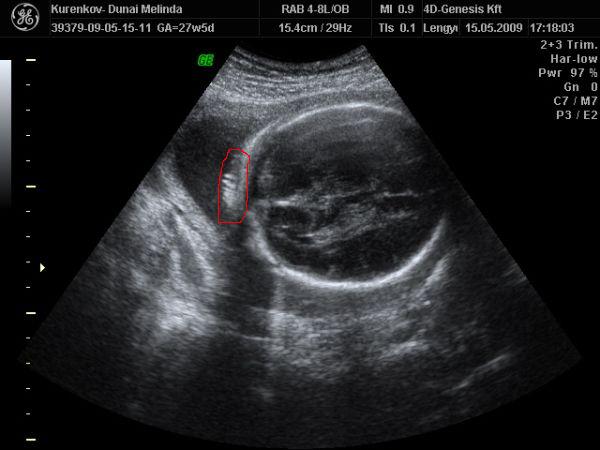

Cscsi:Nagyon aranyos a kis fiad!!És nagyon tündéri a pici babóca is!!!Azt hittem, hogy csak a leányzók tudnak lustizni, de ezek szerint tévedtem!!!A mi pici Leányzónk is, a legutóbbi 4D-n szunyált, és a kis pofiját a méhlepénybe fúrta!!De mi a végén feltudtuk a kis Mazsolát ébreszteni, és sikerült pár jó képet csinálni róla!